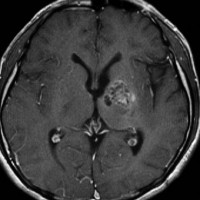

ICE化学療法投与開始から数日で小さくなります

この例は古いので第3脳室開窓術 ETV をしていません。左はICE化学療法前。中央は9日後。右は25日後です。閉塞性水頭症があっても1週間くらいで中脳水道が通って水頭症は改善します。ジャーミノーマであれば,ICE化学療法1コースでかなり縮小するはずです。このような顕著な効果がない時には,逆にジャーミノーマ以外の胚細胞腫瘍が混在していると考えた方がいいでしょう。多くは奇形腫の混在です。